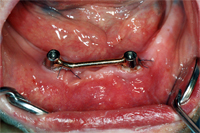

Vier Tage später wird der vom Techniker angefertigte Steg mit den Implantaten verbunden (Abb. 2) und die neue Prothese eingesetzt. Die Patientin hatte weder Schmerzen noch Schwellungen nach der Operation. Eine Woche später kommt die Patientin zur Nachkontrolle und ist total begeistert: "Die Prothese rutscht überhaupt nicht mehr umher und ich kann wieder alles essen. Ja, sogar abbeissen ist wieder möglich!" Die Steghülse, die auf dem Implantatsteg die Vollprothese festklemmt, ist eine sichere Garantie für stabilen Halt der Prothese.

Vier Monate nach Einsetzen der Implantate wird die Unterkieferprothese nochmals unterfüttert und perfekt auf den Kiefer eingepasst. Danach genügen halbjährliche kurze Kontrollen der Implantate, des Stegs und der Prothese. In Abb. 3 ist der Implantatsteg vier Monate nach der Operation sichtbar.